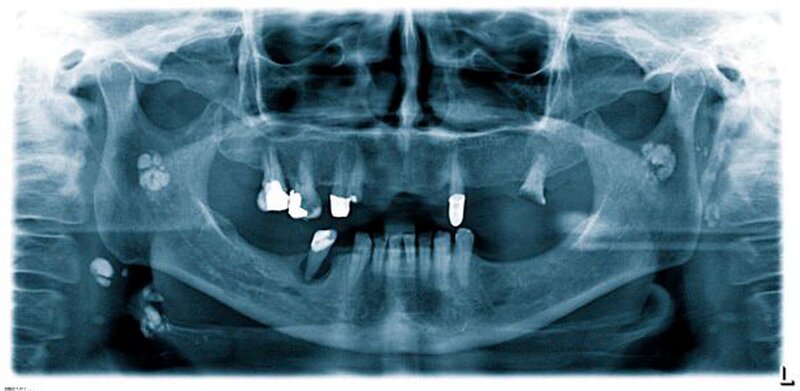

Zur genauen räumlichen Zuordnung der Verschattungen unterhalb der Incisurae semilunares wurde eine dentale digitale volumentomografische Untersuchung durchgeführt (Abbildungen 2 bis 4).

Für die Darstellung von Lymphknoten oder Speichelsteinen stellt die Sonografie die Methode der Wahl dar. In der Regel ist keine Abgrenzung zu weichgeweblichen Strukturen möglich. Dies muss bei kalzifizierenden Metastasen oder hartgewebebildenden Neoplasien (wie Osteosarkome) berücksichtigt werden. Um eine eindeutige Zuordnung zu den umgebenden Weichgewebe-strukturen gewährleisten zu können, sollte eine 3-D-Summationsaufnahme (DVT, CT) durchgeführt werden.

Im vorliegenden Patientenfall war es aufgrund der Anamnese nicht notwendig, weiterführende Untersuchungen (Exzisionsbiopsie) anzuordnen, weil es sich um ossifizierte parotideale Lymphknoten als Folge einer Tuberkulose handelte.